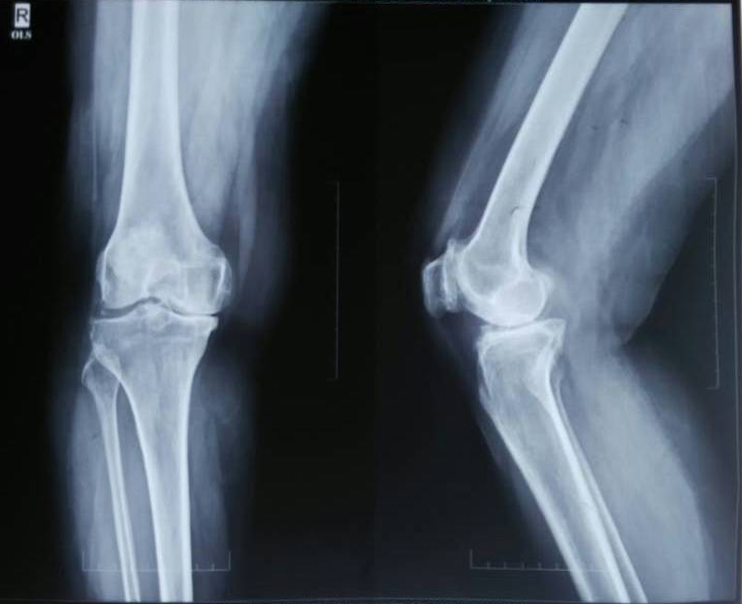

Radiological pictures of severe osteoarthritis

Normal x-ray knee joint

Severe osteoarthritis knee joint

X-Ray 1: Shows the comparative pictures between normal and severe osteoarthritis

X-ray 1 shows the normal knee joint and anteroposterior (AP) view plus a lateral view of the OA affected knee joint. The radiographic hallmarks of primary osteoarthritis include nonuniform joint space loss, osteophyte formation, cyst formation and subchondral sclerosis. At first, only minimal, nonuniform joint space narrowing may be present. The involved joint spaces have an asymmetric distribution.